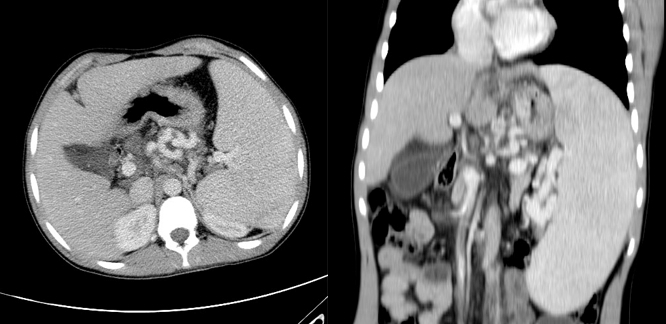

La diagnosi presuntiva al momento è quella di una colangite sclerosante dei piccoli dotti evoluta in cirrosi biliare. La TC evidenzia splenomegalia e varici gastriche ed esofagee (Figura 1). Siamo in attesa dello studio in risonanza magnetica delle vie biliari per chiarire la diagnosi definitiva.